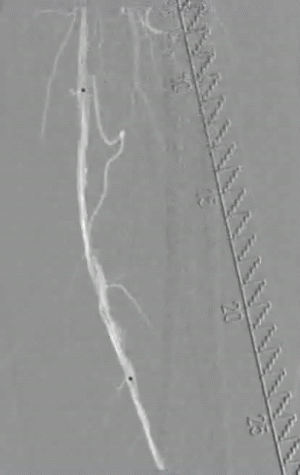

造影显示血流通畅,以5.5×300 mm、5.5×80 mm DCB扩张病变段,扩张时间3 min。

图片

术后造影显示股浅动脉、腘动脉血流通畅,膝下造影同术前。